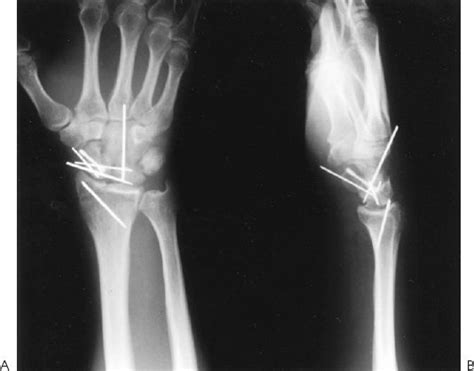

Surgical techniques for ulnar styloid fractures include percutaneous pinning, open reduction internal fixation (ORIF), and arthroscopic-assisted reduction. Percutaneous pinning involves inserting small pins or wires through the skin to stabilize the fracture. ORIF involves making an incision to directly visualize the fracture and stabilize it with plates, screws, or wires. Arthroscopic-assisted reduction involves using a small camera and instruments to visualize the fracture and stabilize it through small incisions.